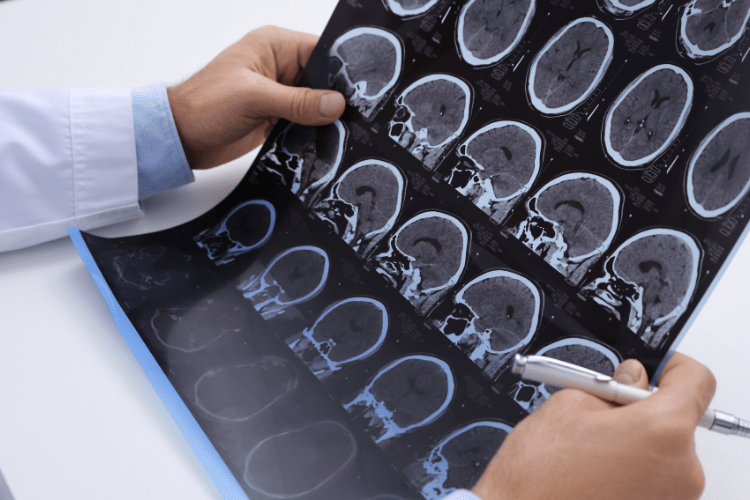

Patologie cerebrali, tra cui tumori benigni e maligni del cervello, ematomi intracranici, idrocefalo e alcune forme di epilessia farmacoresistente, trattate con approcci chirurgici avanzati e tecnologie di navigazione intraoperatoria

Patologie vascolari cerebrali, come aneurismi e malformazioni artero-venose, che possono richiedere interventi chirurgici o trattamenti combinati con tecniche endovascolari

Patologie traumatiche del sistema nervoso, incluse lesioni craniche e vertebro-midollari conseguenti a traumi, che necessitano di un intervento tempestivo e altamente specializzato

Neurochirurgia mini-invasiva e tecniche avanzate, che consentono di trattare numerose patologie con incisioni ridotte, maggiore precisione e tempi di recupero più rapidi, grazie anche all’utilizzo di microscopi operatori, neuronavigazione e tecnologie di imaging intraoperatorio